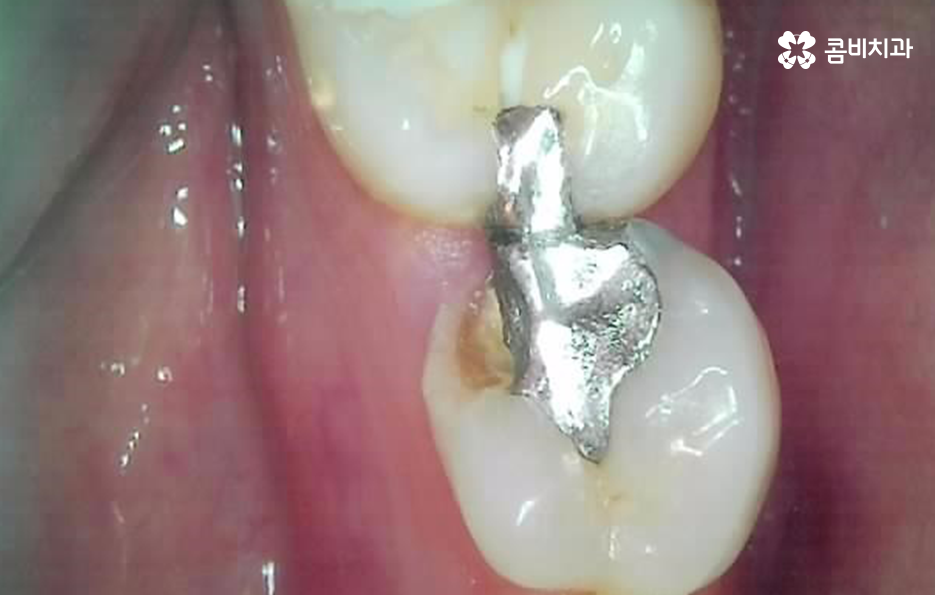

별로 안아팠는데 기존 보철물과 함께 어금니 충치 깨짐이 발생했어요

나이가 들수록 오래된 보철물이 탈락되거나 깨지면서 치아의 손상이 함께 발생되는 사례가 정말 많은데 이러한 문제는 보통 언제 치료를 받았던건지 기억도 안나던 오래된 보철물에서 문제가 발생되는 사례가 많이 있어요

특히 위 환자분의 사례처럼 아말감의 경우에는 빠르고 저렴한 치료 자체는 장점이 있지만 아말감의 특성상 주변 치아가 변색될 우려부터 치아와의 접착이 좀더 빠르게 약해질 우려가 있는 보철물이며 아말감이 조금씩 깨지면서 틈 사이로 충치가 발생되는 사례도 많기 때문에 어금니 충치 깨짐의 경우 보편적으로 보철물 내부에 2차 충치가 발생되면서 치아 내부의 충치가 드러나는 경우가 많고 충치가 없던 경우에는 기존의 치아에 지속적인 마모와 손상이 거듭되다가 치아의 내구성이 약해져서 결국 깨지면서 문제가 드러나는 경우가 많을 거예요